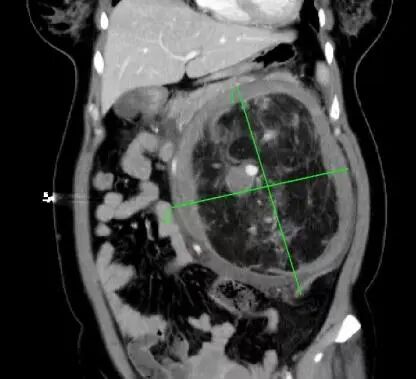

前一段時間,家住惠城區(qū)的林女士(化名)突發(fā)腹痛嘔吐,由120送至惠州市第三人民醫(yī)院急診科。完善全腹部CT后,醫(yī)生發(fā)現(xiàn)患者左腎存在一個巨大腫瘤,直徑約20cm,并伴有破裂出血。

左腎巨大腎錯構瘤約20*20*13cm

隨著超聲檢查在體檢中普及,超過一半的偶發(fā)腎錯構瘤在體檢中被發(fā)現(xiàn),隨后經CT或MRI確診。比如林女士,她的腹部增強CT中可見明顯強化的血管結構和無強化的脂肪組織。